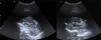

Radiología Solución del caso 30. Papiloma de los plexos coroideos con realce meníngeo

Solución del caso 30. Papiloma de los plexos coroideos con realce meníngeo

Solution to case 30. Choroid plexus papilloma with meningeal enhancement